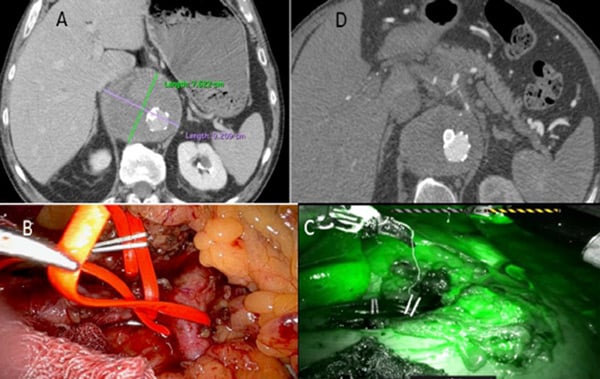

- After pneumoperitoneum induction, the flaccid part was opened and splenic, left gastric and hepatic arteries were identified and carefully isolated.

- The vessels were temporary clamped and green indocyanin was injected to exclude visceral ischemia.

- So, finally, the celiac trunk was closed with a clip at its origin from the aorta.

Robotic celiac trunk ligature

- Type II endoleak (A);

- Celiac branches temporary robotic clamping (B);

- Check with indocyanin green injection (C);

- Type II endoleak complete resolution after celiac trunk ligature (D).

CT-scan follow-up

- Complete type II endoleak resolution

- Absence of visceral ischemia

- No spinal cord ischemia